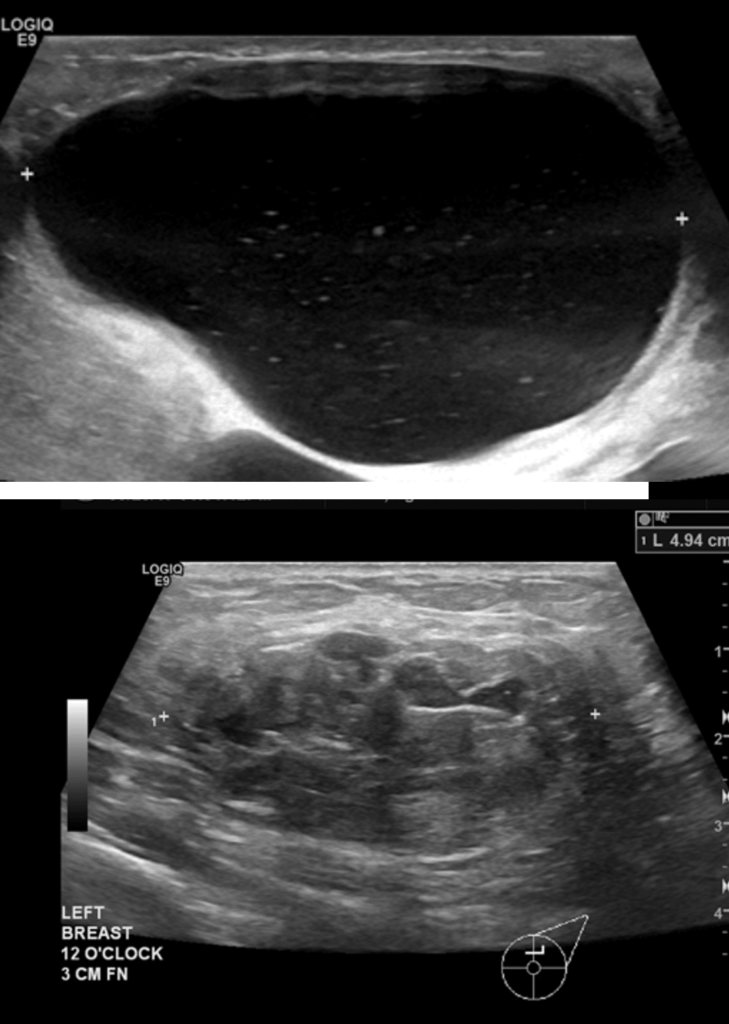

Abscess

One of the first questions people have is “is this an abscess or just mastitis?” While an abscess can be a bit more subtle than these two images above, most of the time it is this obvious. The peeling skin means that the skin is about to breakdown and drain fluid itself. These patients all have a history of a “plug” they were told to “massage to get out” and then pump or feed (or both) to “empty the breast.” Then they end up with a bulging fluid collection. If this sounds like you, you need an ultrasound for diagnosis if you’re not going directly to a surgeon who can diagnose and drain it both.

Phlegmon

A phlegmon is an indistinct area of tissue inflammation, fluid collection, and inflamed capillaries (blood vessels). It can present with redness overlying the area of massage or it can present with a mass-like area in the breast. Ultrasound should confirm the difference between a phlegmon and an abscess (which is a fluid collection that requires drainage).